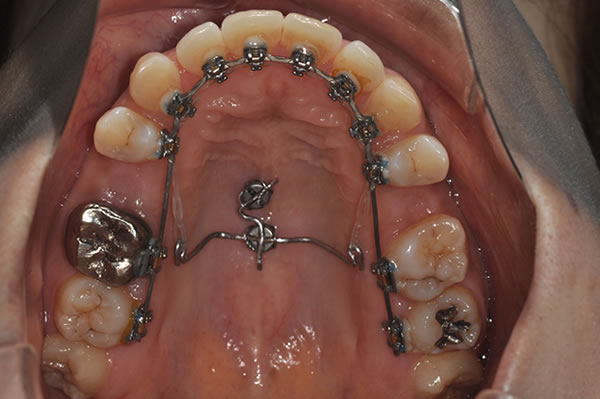

上顎前突症の治療例

上顎前突症(出っ歯)の矯正症例 ケース01

装置 |